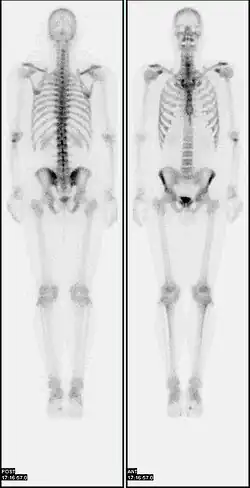

Nuclear medicine (nuclear radiology)[1] is a medical specialty involving the application of radioactive substances in the diagnosis and treatment of disease. Nuclear imaging is, in a sense, radiology done inside out, because it records radiation emitted from within the body rather than radiation that is transmitted through the body from external sources like X-ray generators. In addition, nuclear medicine scans differ from radiology, as the emphasis is not on imaging anatomy, but on the function. For such reason, it is called a physiological imaging modality. Single photon emission computed tomography (SPECT) and positron emission tomography (PET) scans are the two most common imaging modalities in nuclear medicine.[2]

Nuclear medicine tests differ from most other imaging modalities in that nuclear medicine scans primarily show the physiological function of the system being investigated as opposed to traditional anatomical imaging such as CT or MRI. Nuclear medicine imaging studies are generally more organ-, tissue- or disease-specific (e.g.: lungs scan, heart scan, bone scan, brain scan, tumor, infection, Parkinson etc.) than those in conventional radiology imaging, which focus on a particular section of the body (e.g.: chest X-ray, abdomen/pelvis CT scan, head CT scan, etc.). In addition, there are nuclear medicine studies that allow imaging of the whole body based on certain cellular receptors or functions. Examples are whole body PET scans or PET/CT scans, gallium scans, indium white blood cell scans, MIBG and octreotide scans.

Diagnostic tests in nuclear medicine exploit the way that the body handles substances differently when there is disease or pathology present. The radionuclide introduced into the body is often chemically bound to a complex that acts characteristically within the body; this is commonly known as a tracer. In the presence of disease, a tracer will often be distributed around the body and/or processed differently. For example, the ligand methylene-diphosphonate (MDP) can be preferentially taken up by bone. By chemically attaching technetium-99m to MDP, radioactivity can be transported and attached to bone via the hydroxyapatite for imaging. Any increased physiological function, such as due to a fracture in the bone, will usually mean increased concentration of the tracer. This often results in the appearance of a "hot spot", which is a focal increase in radio accumulation or a general increase in radio accumulation throughout the physiological system. Some disease processes result in the exclusion of a tracer, resulting in the appearance of a "cold spot". Many tracer complexes have been developed to image or treat many different organs, glands, and physiological processes.